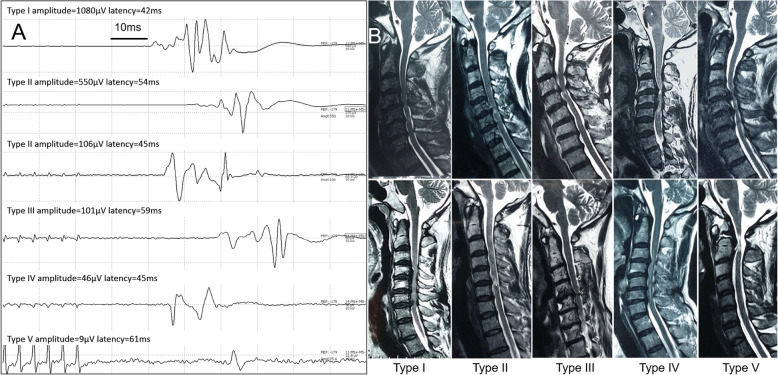

In current study, a different MEP phenotype (Table 2) was firstly addressed for predicting the IONM changes for CCM patients e.g. in Fig. 2.

Fig. 2.

a The representative MEP waveform and parameters among the 5 baseline types. Type II has two subtypes. b The preoperative T2-weighted sagittal magnetic resonance image (MRI) from the patients with different MEP baseline types (Types I, II, III, IV and V)

Type I indicated safe MEP baseline with excellent stability;

Type II also indicated safe MEP baseline with good stability;

Type III was referred to sensitive MEP baseline with average stability;

Type IV was high-sensitive MEP with poor stability;

Type V was indeterminate/high risk MEP baseline.

The MEPs were recorded from the foot muscles (abductor hallucis) for the classification. The MEP types in this study aimed at unilateral baseline, amplitude and latency were considered as peak to peak and the initial of trains’ stimulation to the initial of MEP response respectively. And the baseline classification in Table 2 relies on the MEP stability that is defined based on the amplitude and latency.